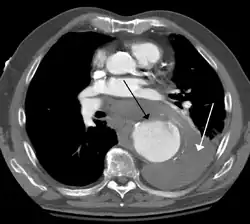

A thoracic aortic aneurysm is an aortic aneurysm that presents primarily in the thorax.

A thoracic aortic aneurysm is the "ballooning" of the upper aspect of the aorta, above the diaphragm. Untreated or unrecognized they can be fatal due to dissection or "popping" of the aneurysm leading to nearly instant death. Thoracic aneurysms are less common than an abdominal aortic aneurysm.[2] However, a syphilitic aneurysm is more likely to be a thoracic aortic aneurysm than an abdominal aortic aneurysm. This condition is commonly treated via a specialized multidisciplinary approach with both vascular surgeons and cardiac surgeons.

Diagnosis

Thoracic aortic aneurysm is defined as a cross-sectional diameter exceeding the following cutoff:

A diameter of 3.5 cm is generally considered dilated.[7] However, average values vary with age and size of the reference population, as well as different segments of the aorta.